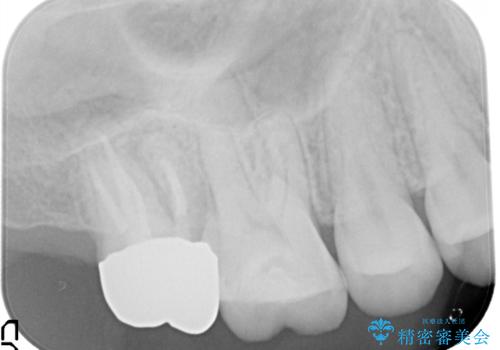

歯肉に埋もれたマージンライン 奥歯の被せもの

以前の被せもののマージンは歯肉縁下に深く形成され、根尖病変も認めたため、根管治療(林先生に依頼)、歯周外科、PGAクラウンにて修復治療を行いました。

妥協せずにすべての治療を行うことで最終的な被せものの適合を高める事ができます。今回のケースを保険の治療で行う場合は長期予後を望めないものとなります。